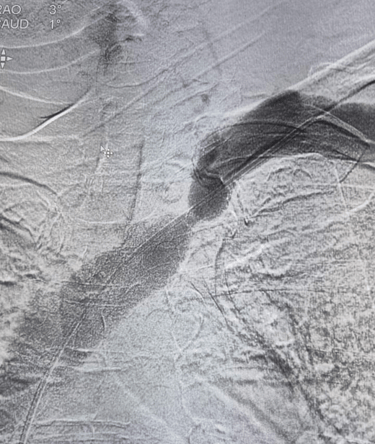

PRE VENOPLASTY